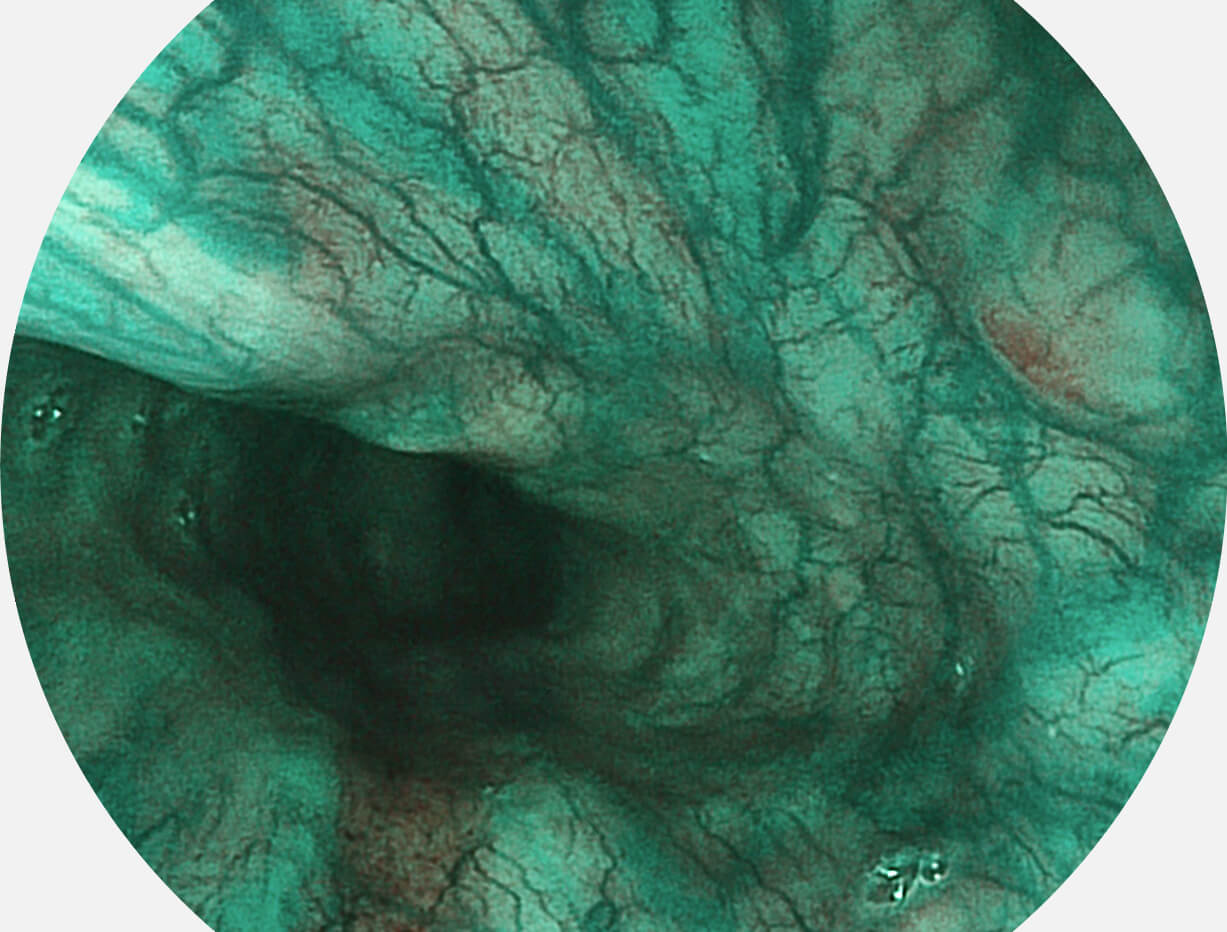

白光图像

VIST图像

强调浅层黏膜结构的同时,保证照明亮度和提升浅层微血管与中层血管颜色对比度,病变边界更清晰。

采用光路合束技术,光谱自由度高,实现了更丰富的照明模式,染色模式SFI及VIST,从远景到近景,助力消化道早期疾病诊断。